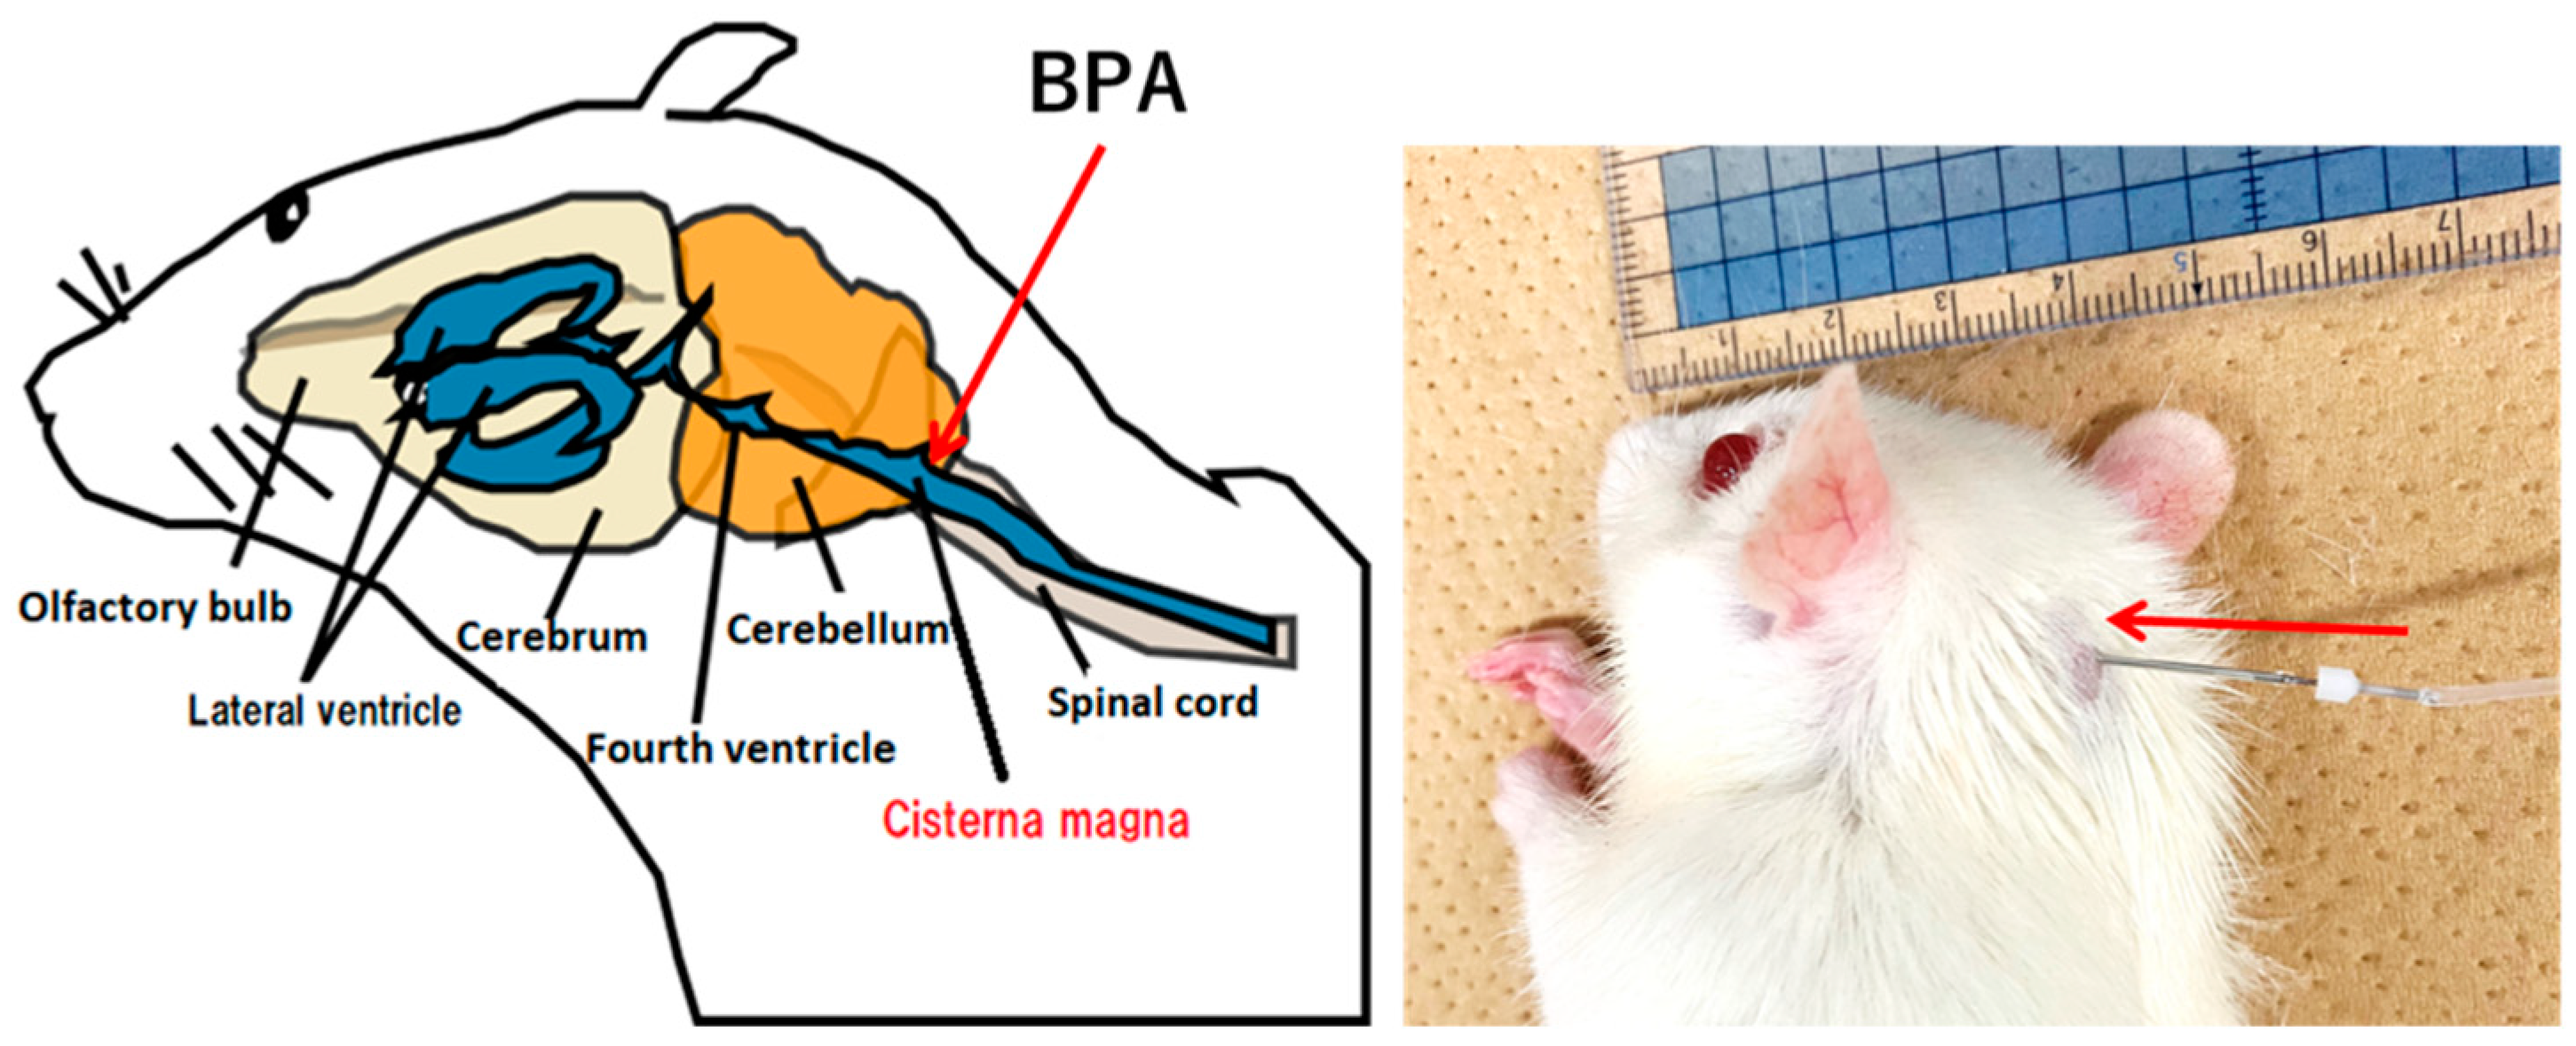

2.2. BNCT Effect on the CSF Administration Method of 10BPA

2.5. Boron Concentrations in Various Normal Tissues of Rat Heads Administered BPA via Both the CSF and IV Methods

- Kusaka, S.; Morizane, Y.; Tokumaru, Y.; Tamaki, S.; Maemunah, I.R.; Akiyama, Y.; Sato, F.; Murata, I. Cerebrospinal fluid-based boron delivery system may help increase the uptake boron for boron neutron capture therapy in veterinary medicine: A preliminary study with normal rat brain cells. Res. Vet. Sci. 2022, 148, 1–6. [Google Scholar] [CrossRef]

- Kusaka, S.; Morizane, Y.; Tokumaru, Y.; Tamaki, S.; Maemunah, I.R.; Akiyama, Y.; Sato, F.; Murata, I. Boron Delivery to Brain Cells via Cerebrospinal Fluid (CSF) Circulation for BNCT in a Rat Melanoma Model. Biology 2022, 11, 397. [Google Scholar] [CrossRef] [PubMed]

- Kusaka, S.; Miyake, Y.; Tokumaru, Y.; Morizane, Y.; Tamaki, S.; Akiyama, Y.; Sato, F.; Murata, I. Boron Delivery to Brain Cells via Cerebrospinal Fluid (CSF) Circulation in BNCT of Brain-Tumor-Model Rats—Ex Vivo Imaging of BPA Using MALDI Mass Spectrometry Imaging. Life 2022, 12, 1786. [Google Scholar] [CrossRef]